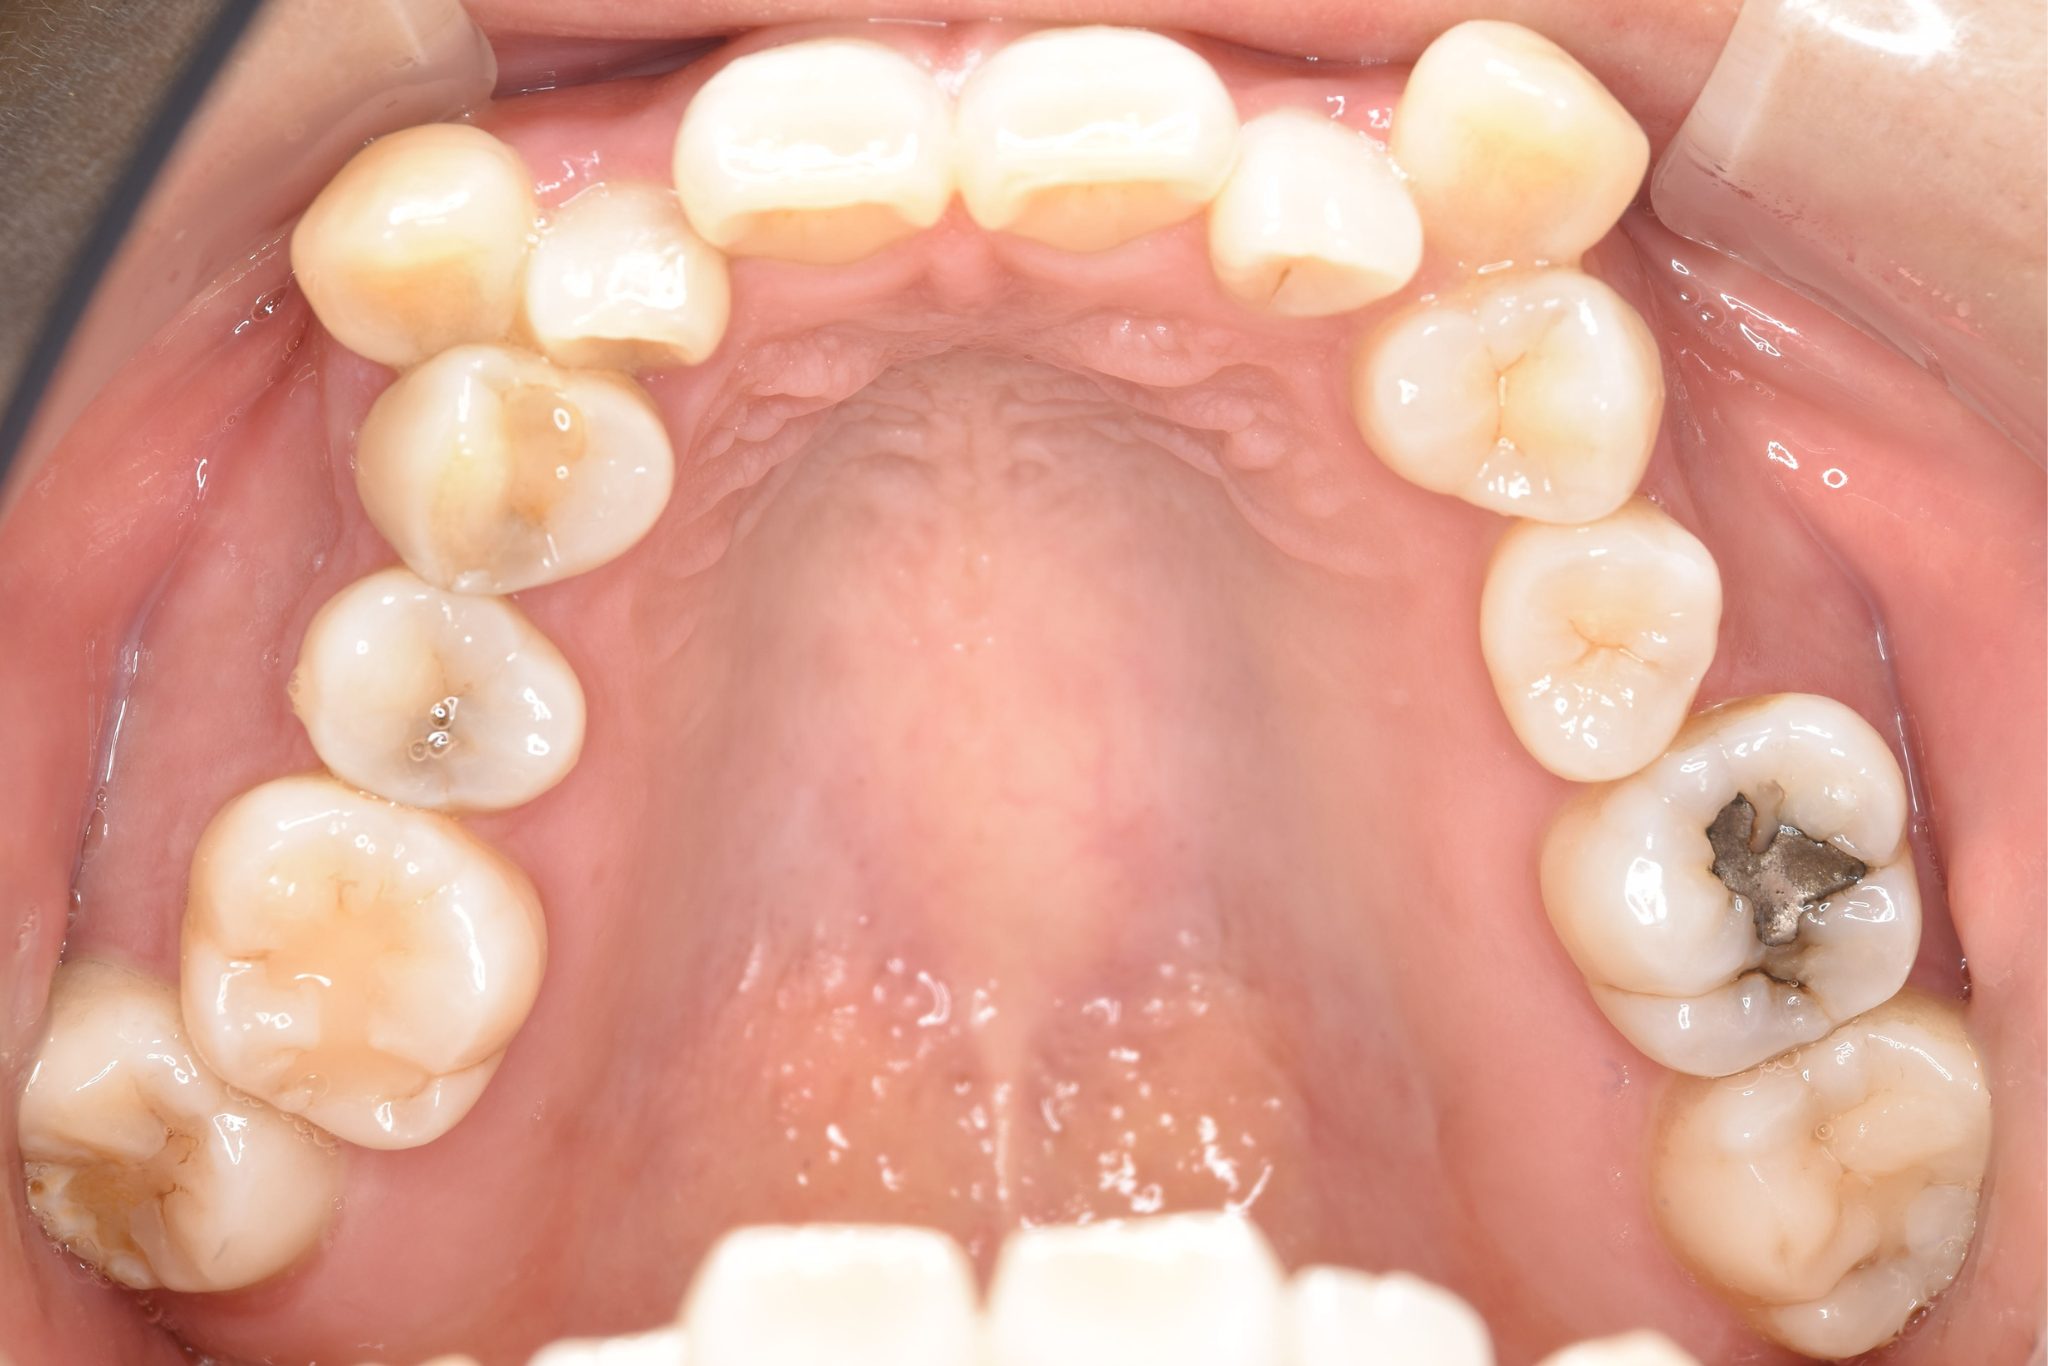

全顎ワイヤー矯正 症例_141 Case

ビフォー

主訴 八重歯|上下センターがずれている

施術内容 成人矯正1期治療

治癒期間 4年10ヶ月間

費用 1,106,560円(税込)

リスク・副作用 違和感、不快感、痛み